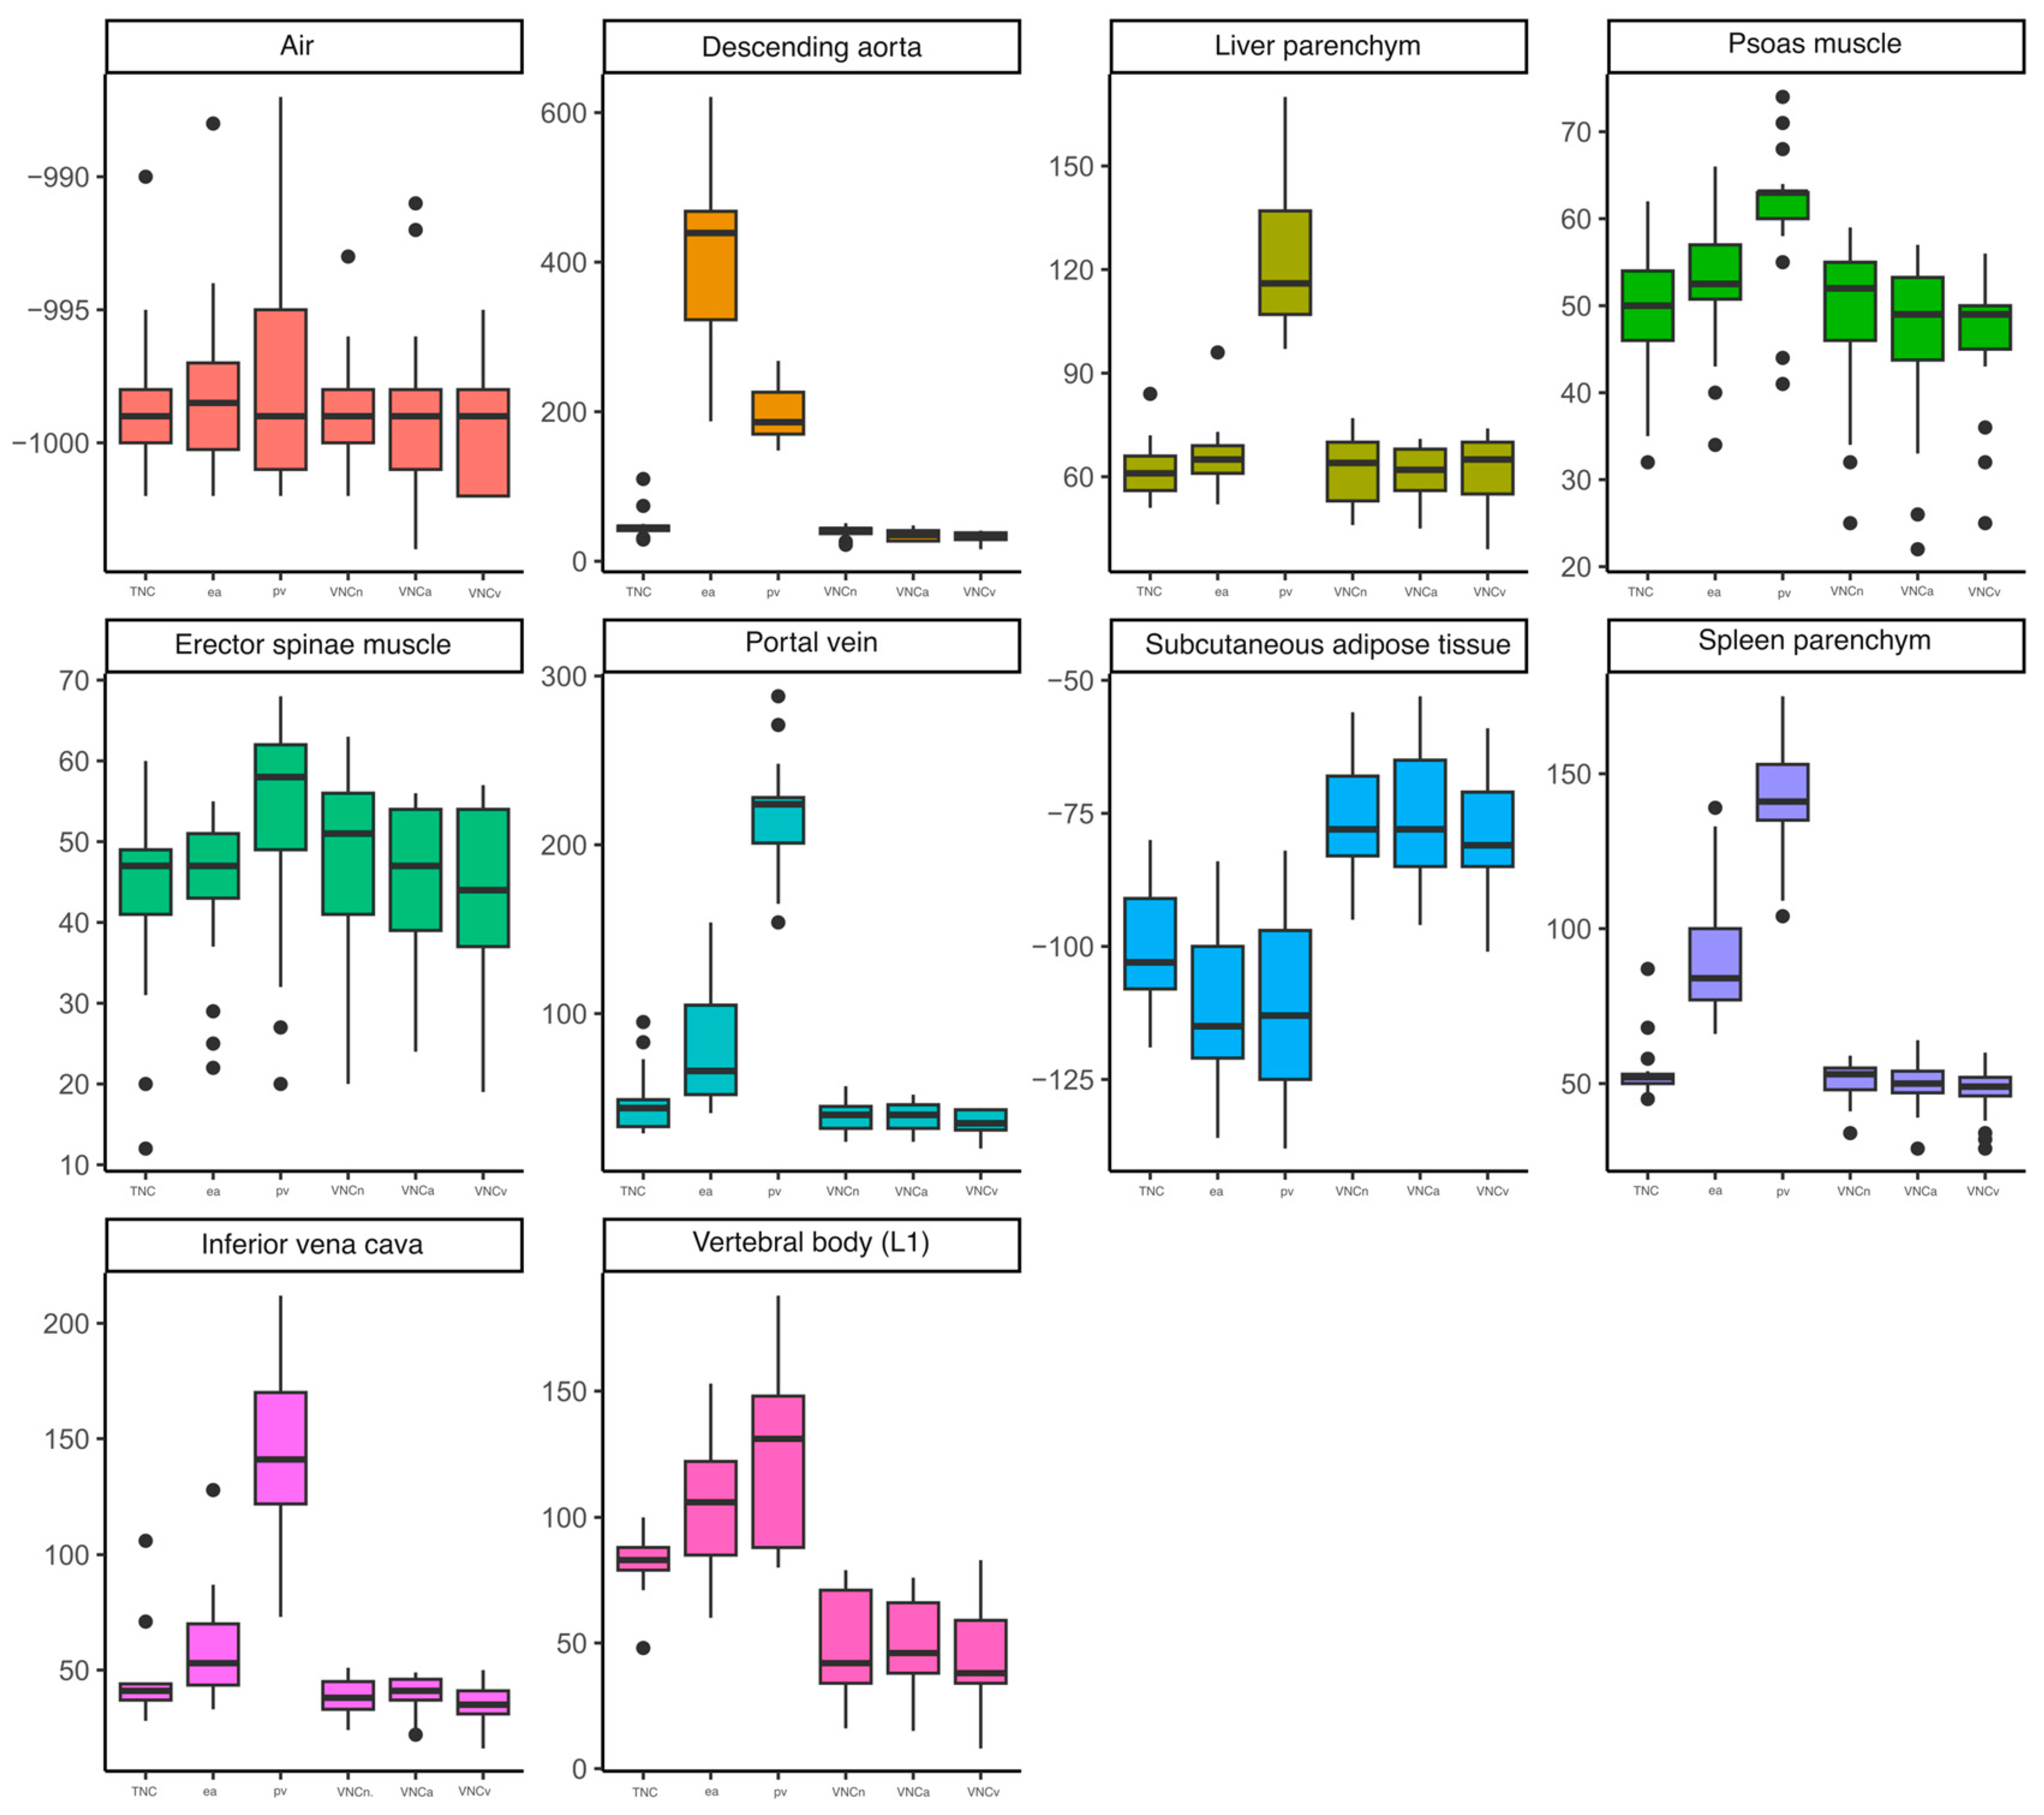

3. Results

3.2. Structured Measurement